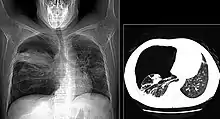

The diagnosis can be confirmed by the characteristic appearance of the chest X-ray and an arterial oxygen level (PaO2) that is strikingly lower than would be expected from symptoms. Gallium 67 scans are also useful in the diagnosis. They are abnormal in about 90% of cases and are often positive before the chest X-ray becomes abnormal. Chest X-ray typically shows widespread pulmonary infiltrates. CT scan may show pulmonary cysts (not to be confused with the cyst-forms of the pathogen).

Chest X-ray of increased opacification (whiteness) in the lower lungs.

These chest radiographs are of two patients. Both show ground glass opacities. The left X-ray shows a much more subtle ground-glass appearance while the right X-ray shows a much more gross ground-glass appearance mimicking pulmonary edema.[7]